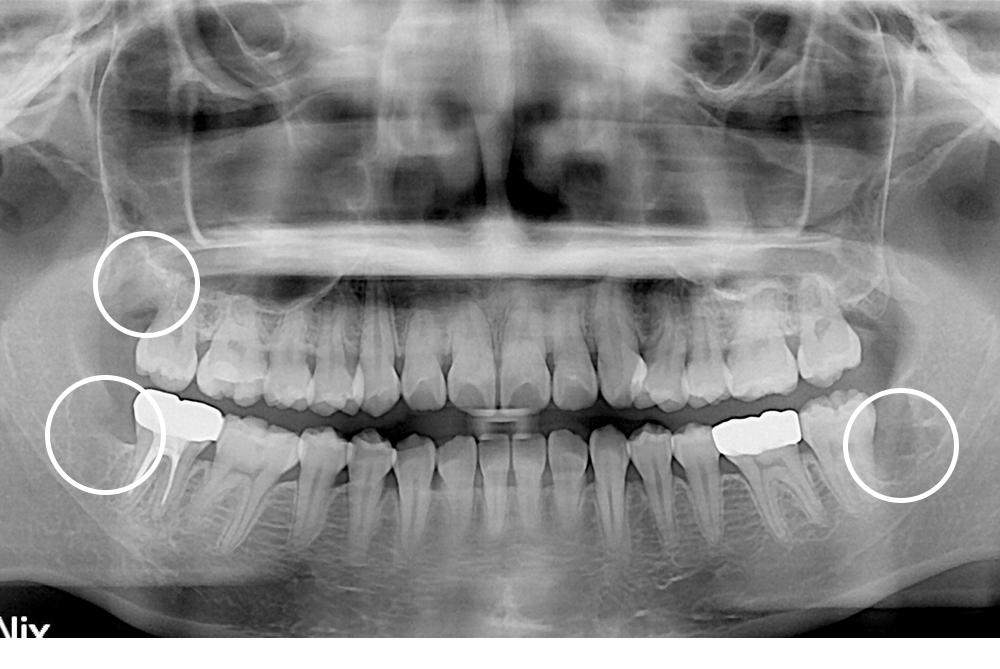

[사랑니] 매복 사랑니 발치

치료후 : 2019-03-08

세종치과는 구강악안면외과학 박사이신 원장님이 발치하는 치과입니다.